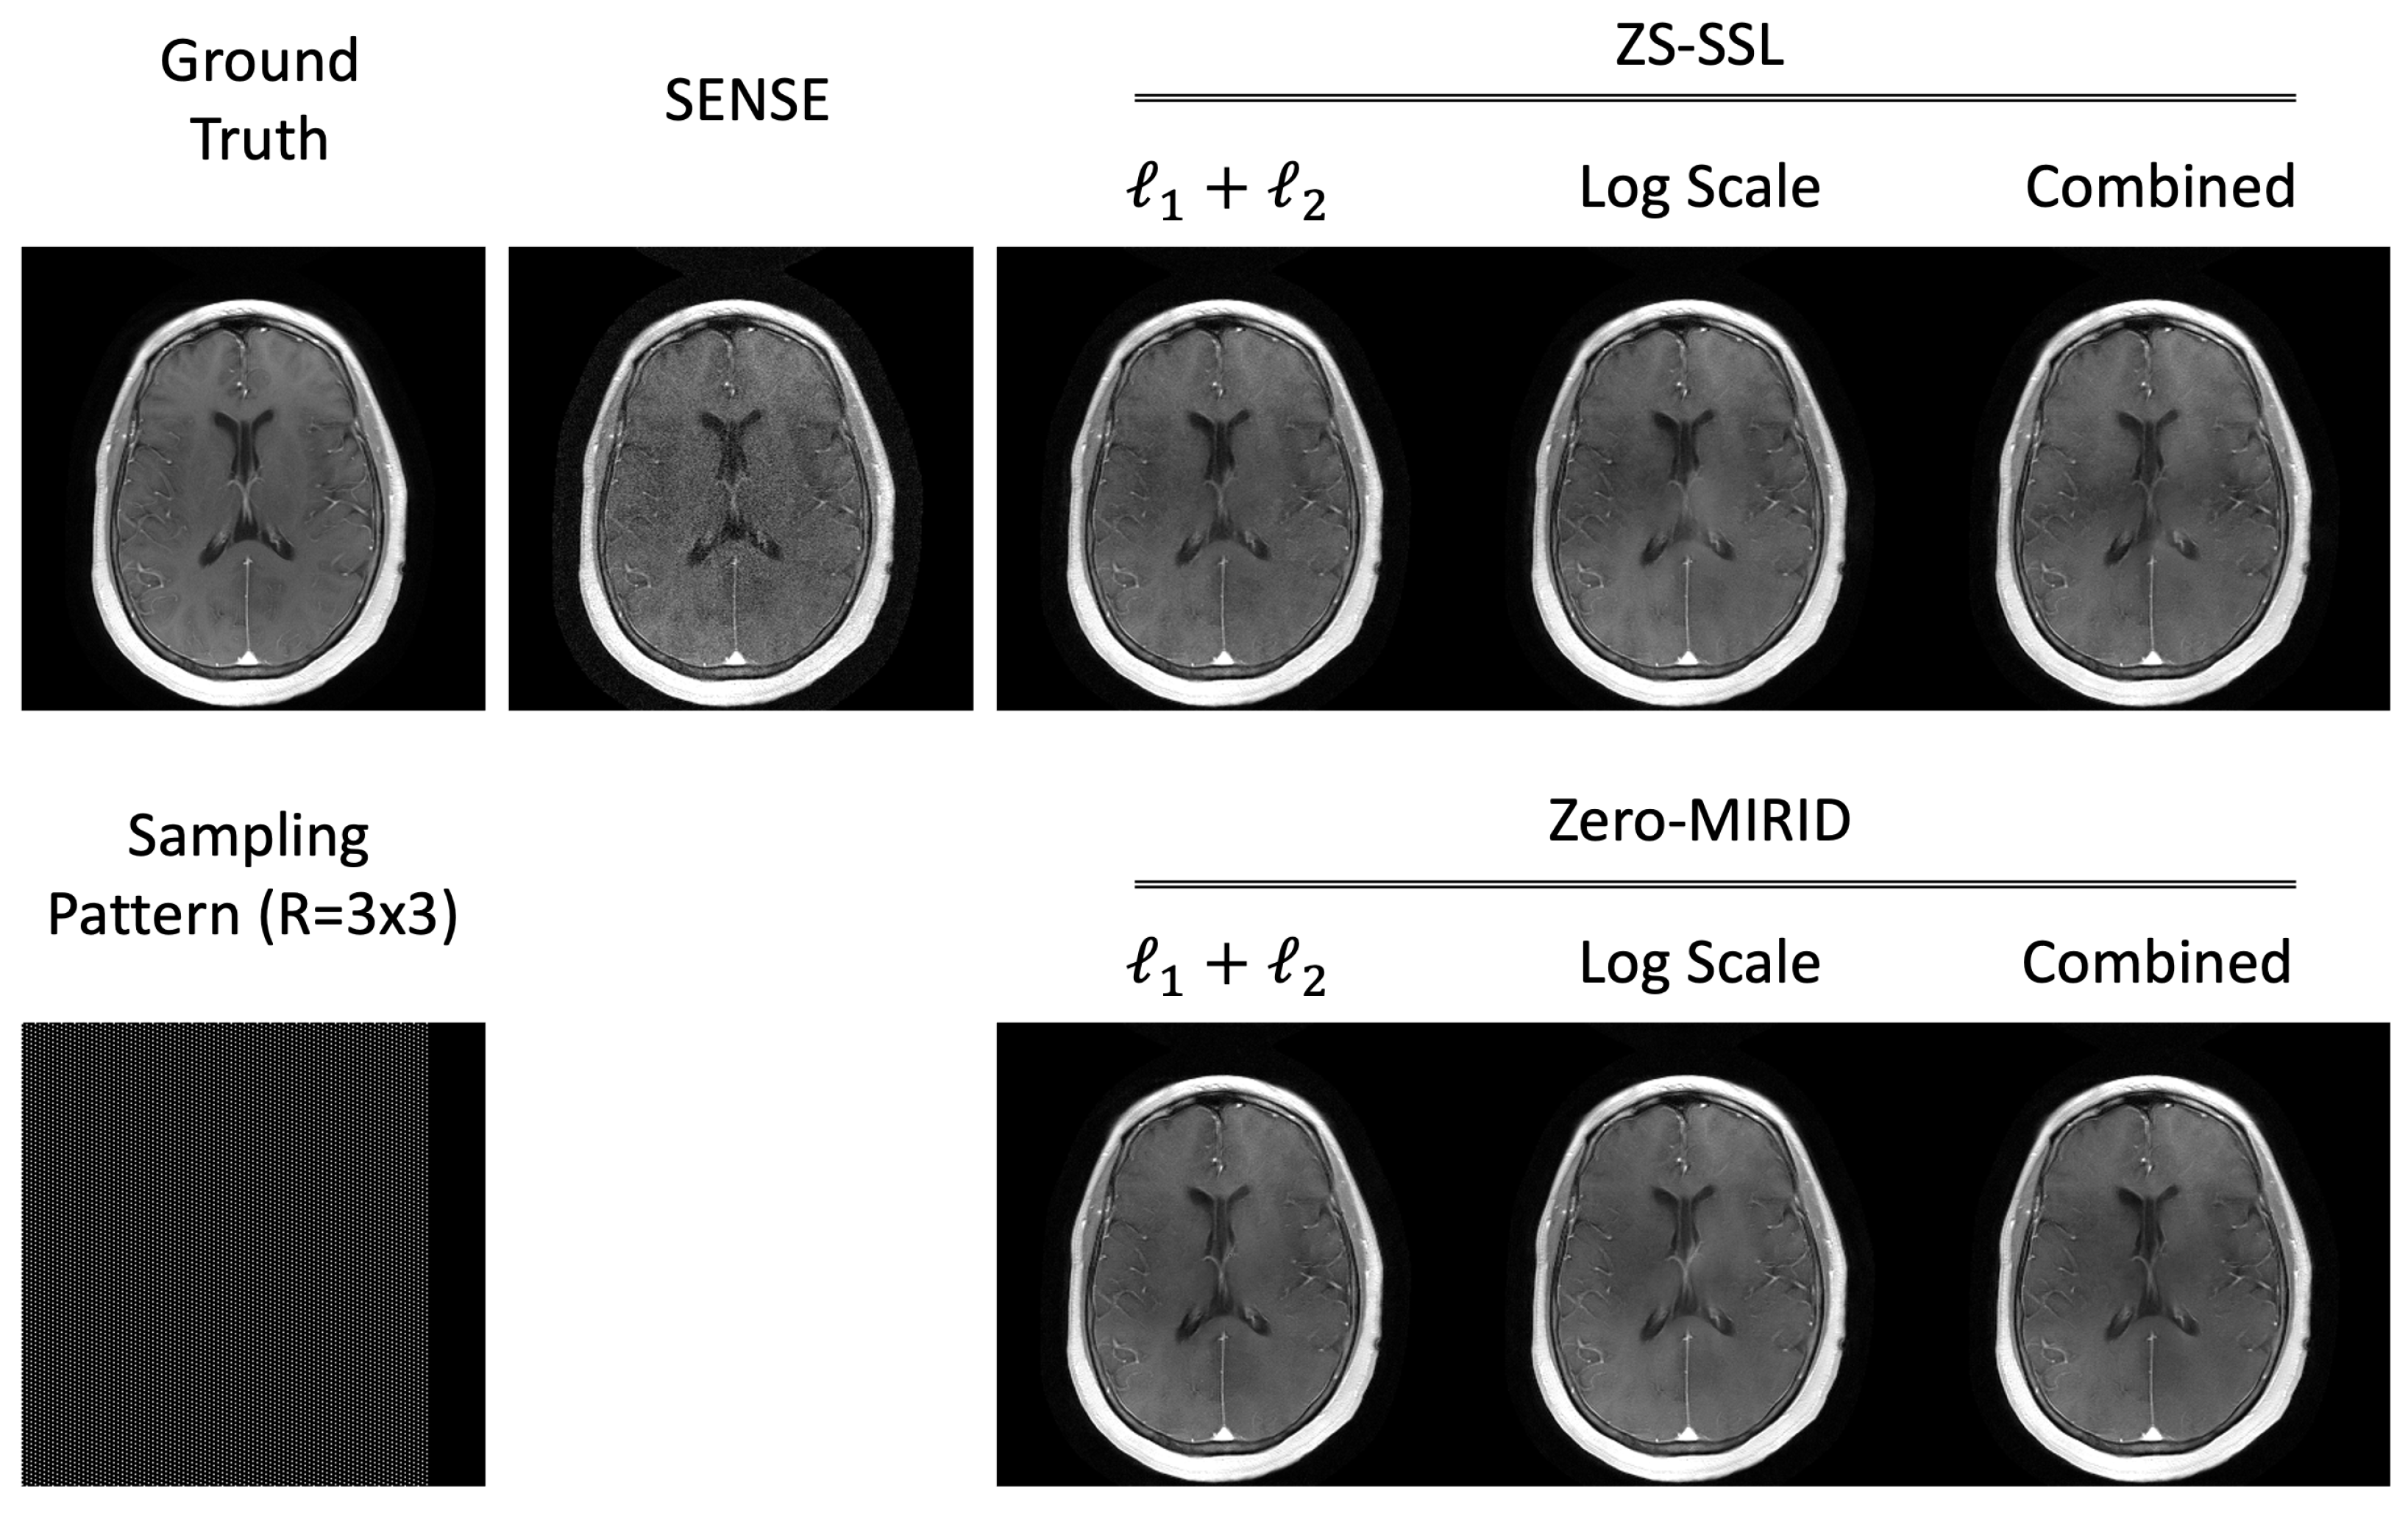

3.2.2. 2D Subsampling

4.2. 2D Subsampling